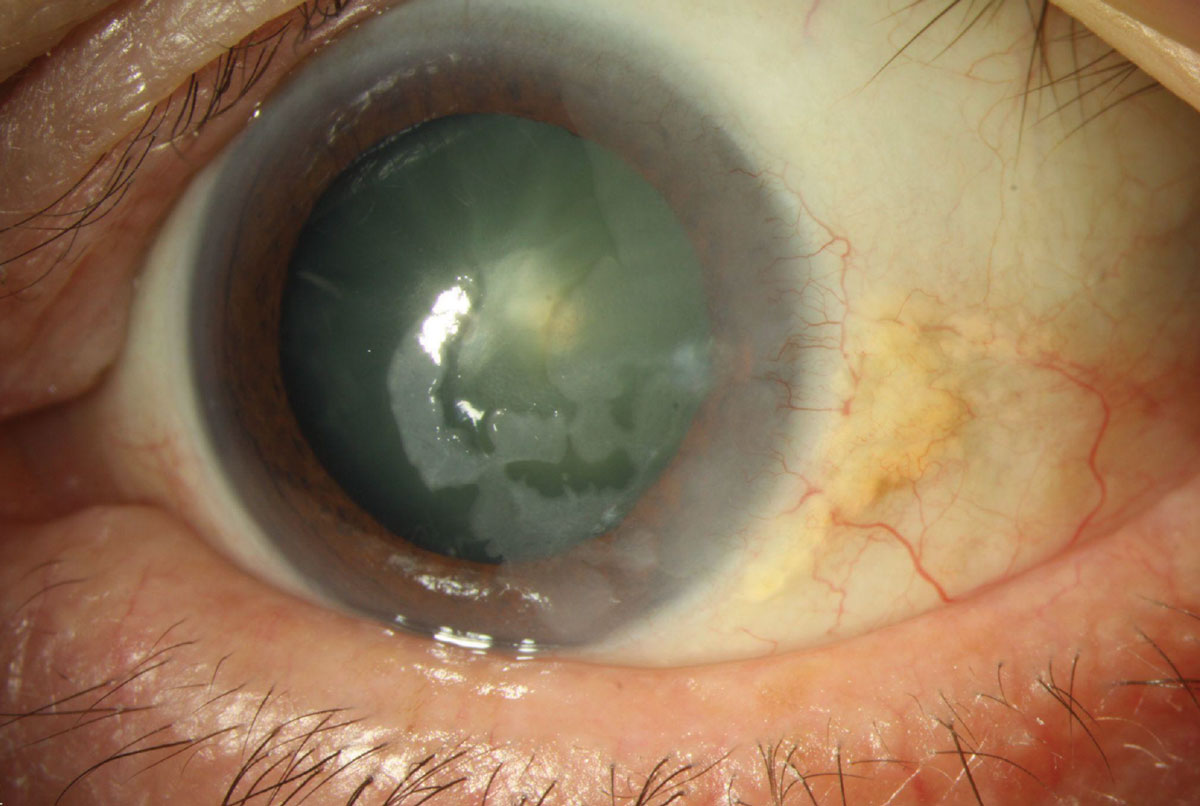

각막상피 이상성숙증(epithelial dysmaturation)은

주로 각막 상피만 침범하는 질환으로 광범위하게

얼어있는듯한 모양의 각막상피 혼탁이 발생하게됩니다.

각막상피의 투명도가 없어지면서 유백색의 병변으로 상피의 혼탁이 관찰되며,

주로 각막 상피만을 침범합니다.

이는 양성의 병변으로 서서히 진행하거나, 그대로 유지되며,

조직학적으로 핵크기만 다른, 정상과 비슷한 상피세포가 관찰됩니다.

치료는 긁어내거나 각막윤부를 포함한 광범위 절제로 가능하나,

표층 각막 절제술을 시행시 보우만막을 제거하면 혼탁이 더 심해지므로 주의해야합니다.